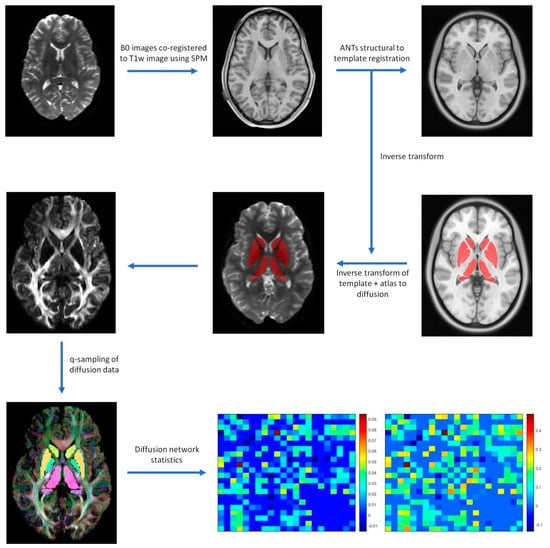

2.3. Image Processing

2.4. Diffusion Processing